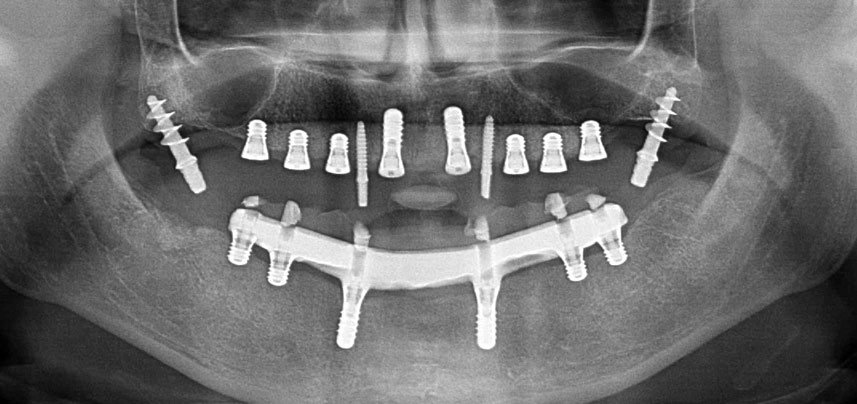

Tre anni dopo era il momento di una protesi dentaria mascellare dello stesso tipo. In base alla pianificazione con CBCT, il rialzo del seno mascellare è stato evitato con l'ausilio di impianti corti e una dima chirurgica è stata utilizzata per trasferire le posizioni pianificate alla cresta alveolare (Figg. 1 e 2).

Radiografia panoramica postoperatoria

Fig. 10: La radiografia panoramica postoperatoria mostra tutti gli impianti nelle posizioni appropriate, inclusi gli impianti provvisori pterigoidei.